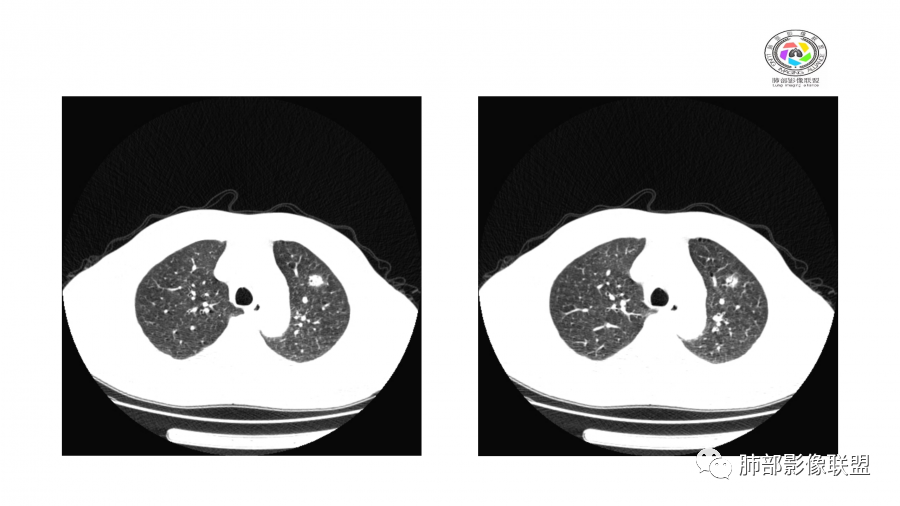

10天后:病灶继续吸收好转

伴随少量胸水

应该与气道无关

符合间质、血管来源病变

此起彼伏

有肾功能不全

支持与肾病相关

警惕血管炎

隐球菌不支持